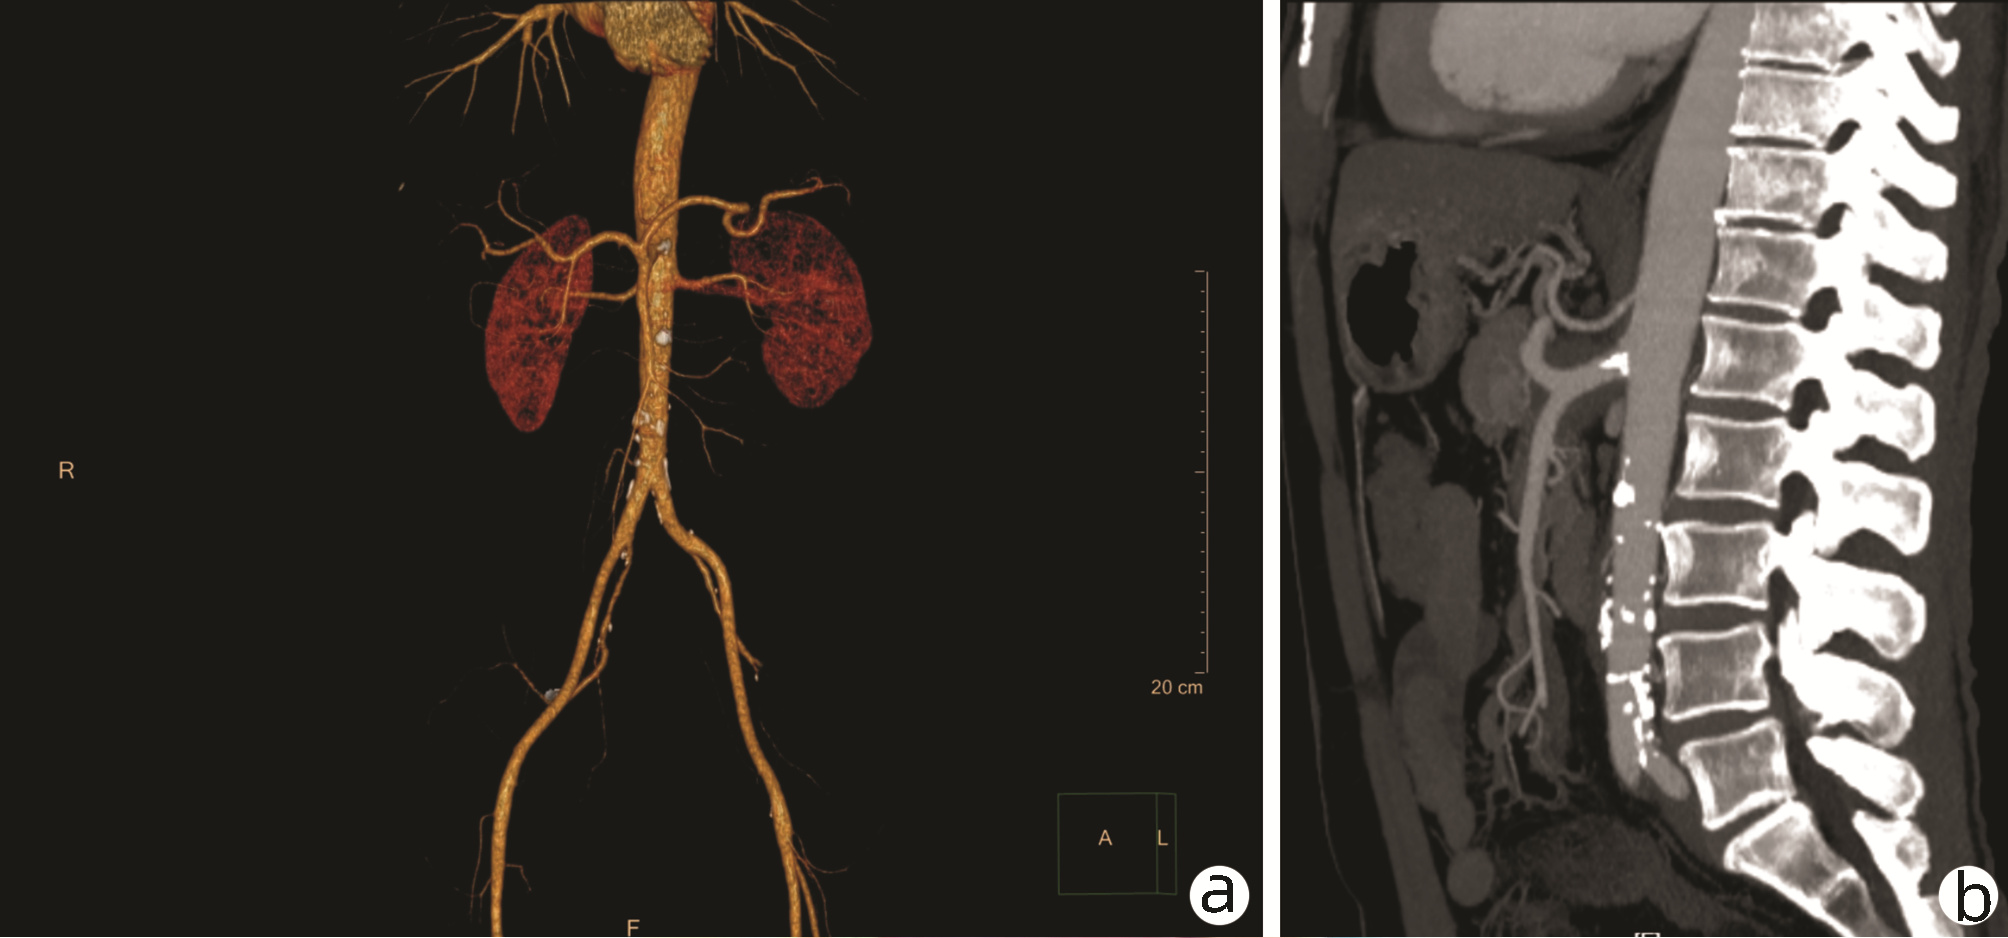

乙型肝炎肝硬化上消化道出血的ΔCT特征性表现及预测模型的建立

李俊杰, 孙岩岩, 李将宏, 郑虹

2022, 38(5): 1081-1085. DOI: 10.3969/j.issn.1001-5256.2022.05.020

摘要(1053) HTML (308) PDF (2671KB)(64)

摘要:

目的  本研究旨在寻找乙型肝炎肝硬化CT特征,建立肝硬化上消化道出血预测模型,预测出血风险。  方法  回顾性分析2015年1月—2021年6月天津市第一中心医院101例型肝炎肝硬化患者的数据,将其分为上消化道出血组(P=58)及非出血组(n=43)。比较两组间实验室检查以及强化CT检查测的平扫期、动脉期、门脉期以及静脉期的CT值,并计算各期间CT值的变化(ΔCT)。计量资料两组间的比较使用t检验或Mann-Whitney U检验;使用logistic回归分析方法,预测相关危险因素;通过计算受试者工作特征曲线下的面积评估模型辨别力,而模型校准则通过Hosmer-Lemeshow确定。在多变量logistic回归分析结果的基础上,使用Rstudio4.1.2软件的R包构建预测的列线图模型,并绘制相应的ROC曲线、校准曲线以及临床决策曲线。  结果  非出血组血清TBil、WBC、PLT水平与出血组比较,差异均有统计学意义(P值均<0.05);两组在肝-Plain、脾-P-Plain、脾-P-A ΔCT值存在统计学差异(P值均<0.05)。单因素logistic分析结果显示,白细胞(OR=0.770,95%CI:0.624~0952, P=0.016)、血小板(OR=0.979,95%CI:0.965~0.994, P=0.006)、肝脏平扫期(OR=1.142,95%CI:1.058~1.233, P=0.001)、脾脏门脉期-平扫ΔCT值(OR=0.979,95%CI:0.959~1.000, P=0.050)、脾脏门脉期-动脉期ΔCT值(OR=0.979,95%CI:0.944~0.994, P=0.015)在乙型肝炎肝硬化患者发生上消化道出血与未出血两者之间差异具有统计学意义。多因素logistic分析结果显示血小板(OR=0.968,95%CI:0.944~0.993, P=0.011)、肝脏平扫期(OR=1.148,95%CI:1.047~1.259, P=0.003)、脾脏门脉期-动脉期ΔCT值(OR=0.951,95%CI:0.908~0.995, P=0.030)为上消化道出血的独立危险因素。基于多因素logistic分析结果,构建了乙型肝炎肝硬化上消化道出血的预测模型并绘制校准曲线。该模型的受试者特征曲线下面积为0.801,cut-off值为0.433,其对应的敏感度是81.4%,特异度是77.6%。模型的校准曲线与理想曲线贴合良好。  结论  乙型肝炎肝硬化肝脏具有特殊的ΔCT变化,通过ΔCT构建的预测模型对于乙型肝炎肝硬化上消化道出血具有良好的预测能力。